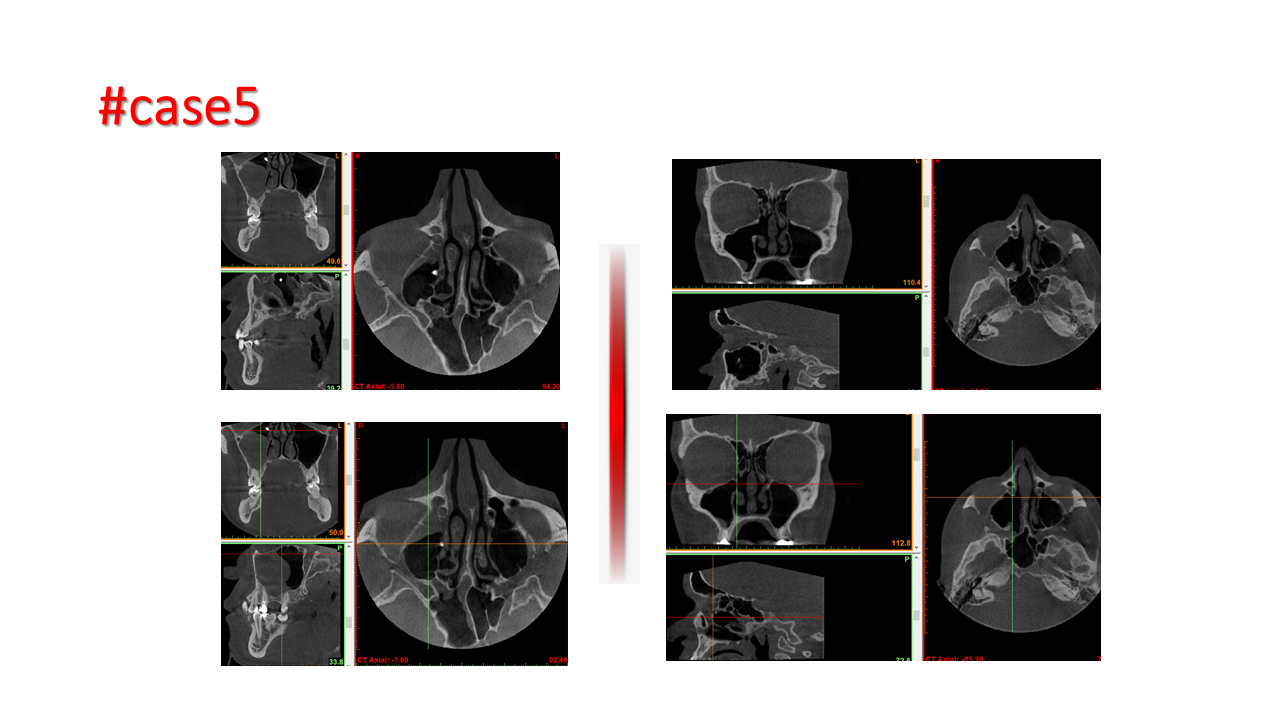

FESS Case Review and Radiologic Analysis (30.09.2016)

Case-based presentation focused on pre- and postoperative imaging in functional endoscopic sinus surgery (FESS). Includes anatomical landmarks, surgical variations, sinus pathology, and technique evaluation. Delivered by Dr. Levon Galstyan at AAOMFS.